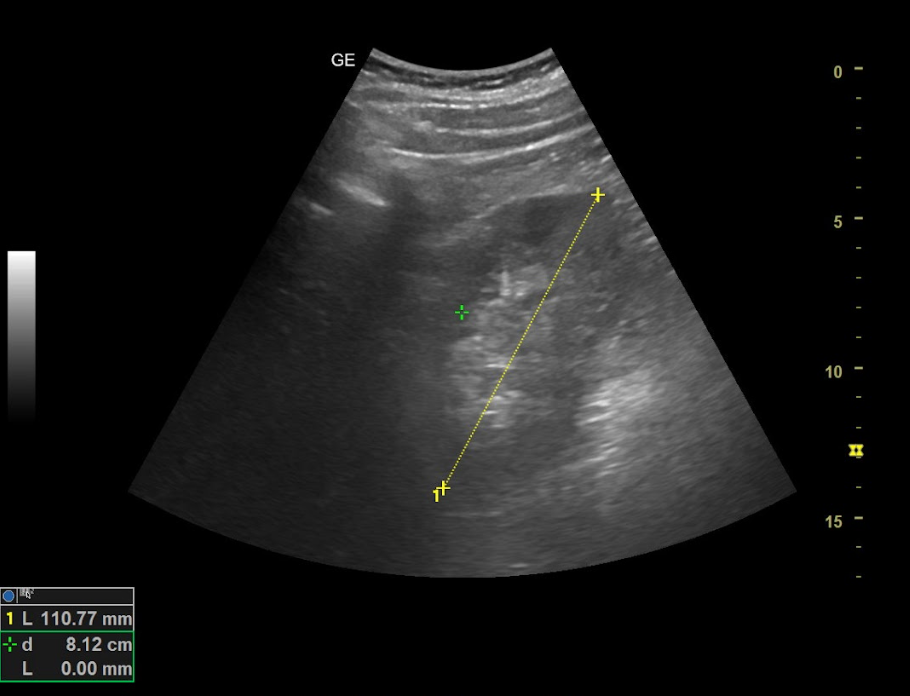

Hallazgos ecográficos

Ambos riñones son de tamaño similar considerándose normales y no apreciando hidronefrosis asociada. En el interior del riñón derecho se aprecia litiasis renal única que proyecta sombra posterior de diámetro máximo de 8,68 mm y potencial responsable del cuadro.